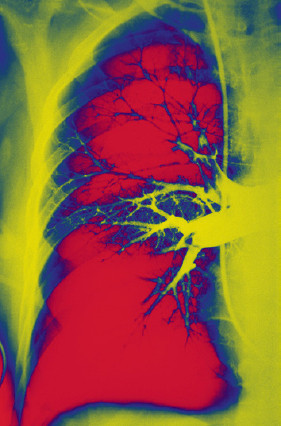

Kennistoets: Diagnostische vertraging bij longembolie

Diagnostische vertraging tussen de eerste klachtenpresentatie en de diagnose ‘longembolie’ komt frequent voor in de huisartsenpraktijk. Toets uw kennis.